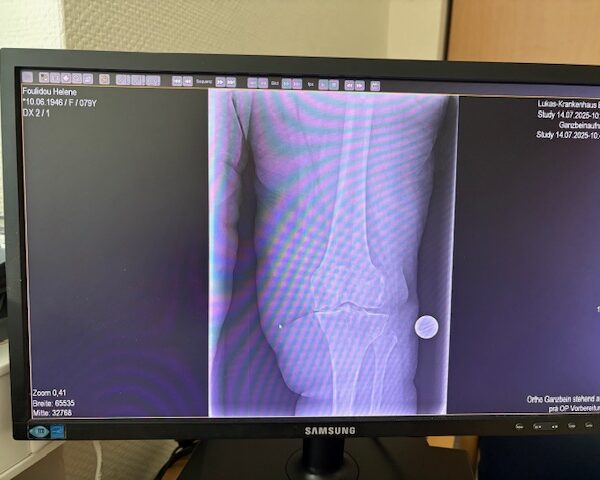

Η 80χρονη ασθενής παρουσίαζε έντονο πόνο και δυσκαμψία στο αριστερό γόνατο τα τελευταία χρόνια. Ο πόνος είχε επιδεινωθεί, επηρεάζοντας τη βάδιση και τη συνολική κινητικότητα, ενώ δυσκολευόταν ακόμα και σε απλές δραστηριότητες όπως το ανέβασμα σκαλοπατιών ή το περπάτημα σε μικρές αποστάσεις. Με την υπάρχουσα πρόθεση ισχίου στην αριστερή πλευρά η ασθενής ήταν αρκετά ευχαριστημένη. Ο ακτινολογικός και κλινικός έλεγχος ανέδειξε προχωρημένη οστεοαρθρίτιδα του αριστερού γόνατος, με πλήρη απώλεια του αρθρικού χόνδρου και παραμόρφωση του μηροκνημιαίου άξονα. Μετά από ανάλυση όλων των επιλογών, αποφασίστηκε η Ολική Αρθροπλαστική Γόνατος με Ρομποτική Υποβοήθηση, με στόχο την απόλυτη ακρίβεια στην τοποθέτηση των εμφυτευμάτων και την αποκατάσταση της φυσιολογικής μηχανικής του γόνατος.

Ο προεγχειρητικός ψηφιακός σχεδιασμός

Πραγματοποιήθηκε σε ειδική ακτινογραφία ολόκληρων των δύο κάτω άκρων. Σε αυτό το ψηφιακό μοντέλο σχεδιάστηκε με ακρίβεια το είδος, το μέγεθος και η ακριβής θέση των προθέσεων, με βάση τα ανατομικά χαρακτηριστικά της ασθενούς.